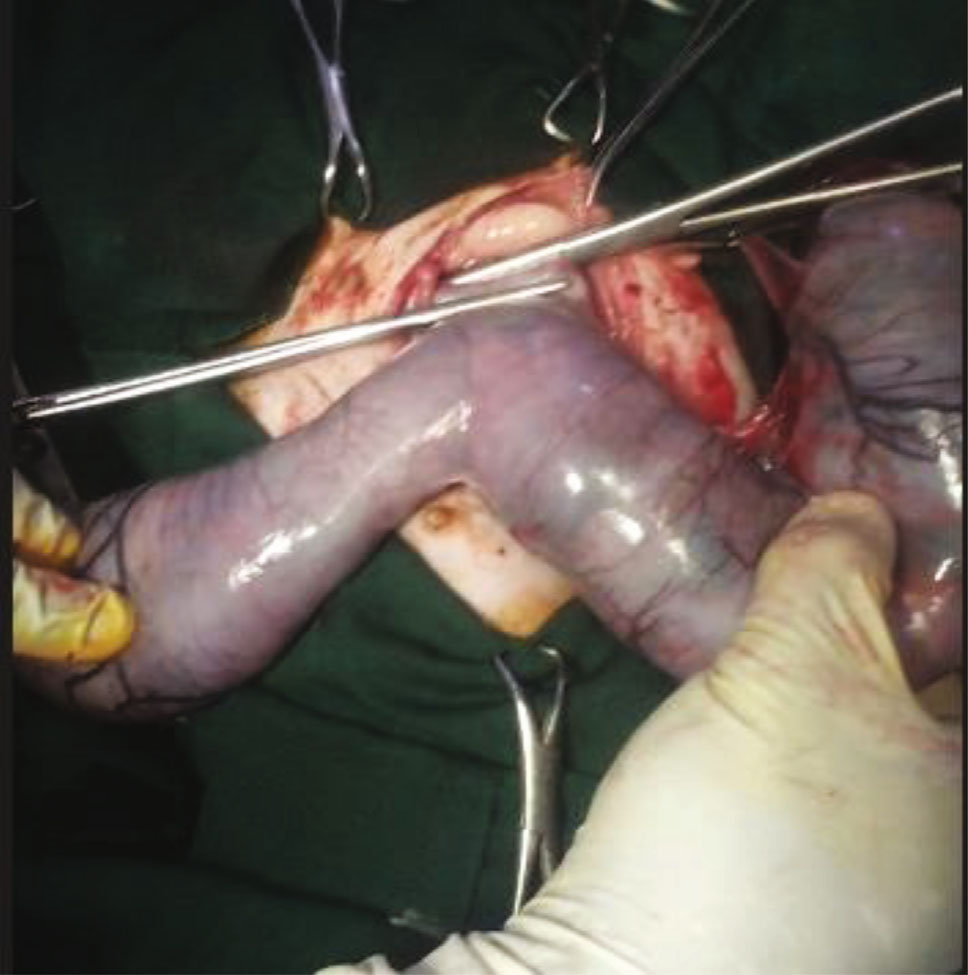

助手立即切开子宫并取出两个死去的公猫(下图)。检查子宫残端是否有出血并还纳入腹腔。腹壁,包括腹膜和白线,使用2-0缝线缝合。皮下组织和皮肤分别缝合。手术总时间约为30分钟。

↑ 从子宫中取出的两个死去的雄性胎儿。